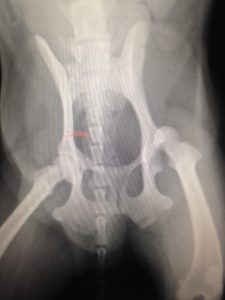

さて、本日ご紹介する症例は、股関節脱臼です。

来院したのは10歳のトイプードルの男のコ。

ソファからジャンプした時に着地に失敗し、

後ろ脚がケンケンするような歩き方になったとのこと。

レントゲンを撮影すると、左後脚の股関節脱臼と判明しました。

股関節整復手術後、ギプスで固定しましたが、10日後、再脱臼。

原因は、骨頭と股関節を結ぶ靱帯が切れてしまっていたか、

脱臼時の衝撃で関節包(関節を包んでいる袋状の皮膜)が損傷してしまっていたため。

4時間におよぶ再手術で破れた関節包を縫い合わせ、

再度、脱臼しないように2本のピンで大腿骨を腸骨に固定することに。

身体の外側に出たピンを輪ゴムで固定する方法を選択しました。